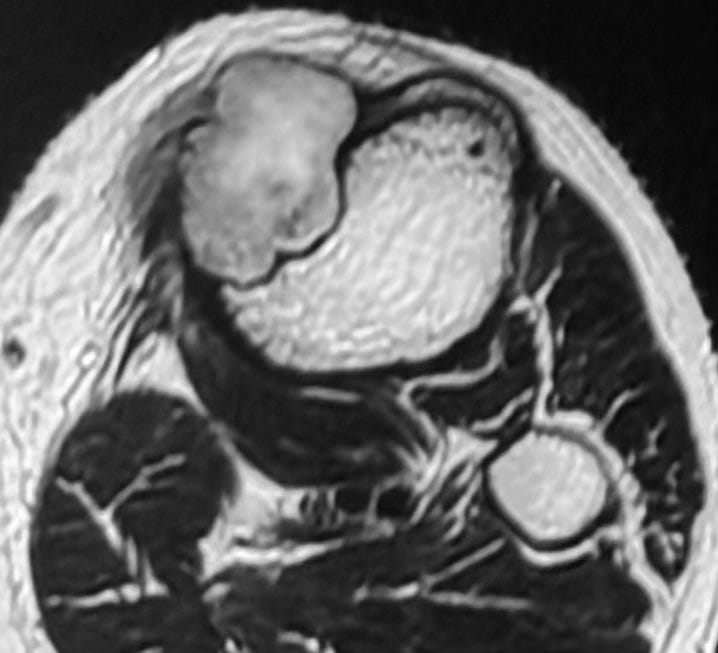

Case:

25-years old with knee pain.

X-ray shows an osteolytic lesion with a sclerotic rim - this is a benign lesion.

MRI shows marrow edema - this is now a “benign aggressive” lesion.

The lesion is partly T2 dark and shows a lamellated pattern of enhancement and is eccentric juxtamedullary.

A biopsy was done.

The findings are characteristic of chondromyxoid fibroma.